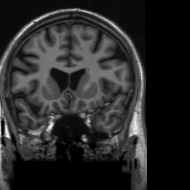

4.3 Medical Image Compressive Sensing

Medical image compressive sensing is an everlasting practical application in image reconstruction area. In this section we test the performance of the proposed ResGD-Net on compressive sensing reconstruction of brain MR images [3] (CS-MRI). In CS-MRI problem, the data fidelity term is , where , is a binary selection matrix representating the sampling trajectory, and is the discrete Fourier transform. We randomly pick images from the brain MRI datasets [3], then crop and keep the central part with less background. Then we at random divide the dataset to images for training and for testing. Among this section, we present the comparison results between ResGD-Net and ISTA-Net+ [33], where the latter one is a state-of-the-art method in tackling with CS-MRI problem. For fairness, both algorithms compared here are evaluated on the same dataset and metrics. Experiments are conducted across different sampling ratios , and of to show the generality. The study of ResGD-Net on different sampling ratios and various phase numbers is shown in Fig. 4. The PSNR comparison with ISTA-Net+ is shown in Table. 2. The result enhancement of the proposed ResGD-Net against ISTA-Net+ is remarkable across all sampling ratios even though we only use approximately many number of parameters than ISTA-Net+ [33].

In addition, we provide the visualization results of some selected MR images reconstructed by the state-of-the-art ISTA-Net+ [33] and our proposed ResGD-Net on compressive sensing (CS) ratio , and . The results are evaluated under metrics the Peak Signal-to-Noise Ratio (PSNR), the Structural Similarity (SSIM) and the Mean Squared Error (MSE). For better visualization, we rescale the pixel value by multiplying on the error maps (the second row of Figs. 5 - 7) when displaying.

PSNR: dB

SSIM:

MSE:

PSNR: dB

SSIM:

MSE:

PSNR: dB

SSIM:

MSE:

PSNR: dB

SSIM:

MSE:

PSNR: dB

SSIM:

MSE:

PSNR: dB

SSIM:

MSE: